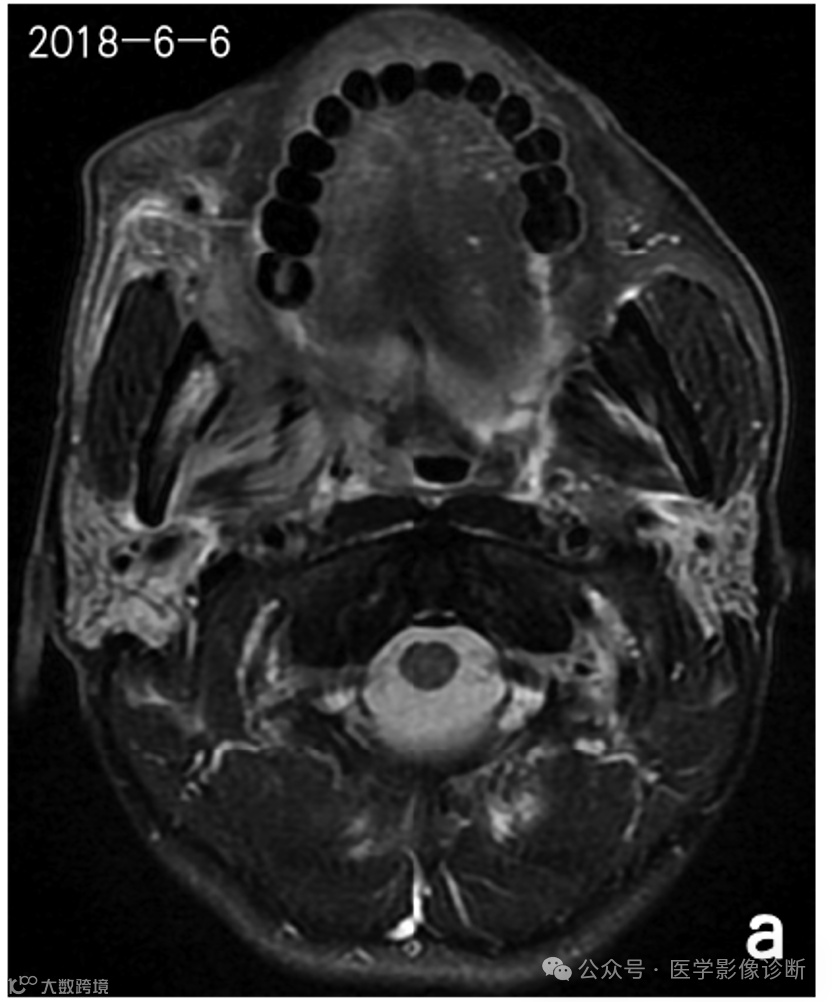

患者,男性,56岁,放疗后患有右口咽癌。

不同时期的四次核磁共振成像显示右下颌骨有异常信号。前两次报告(a、b)均未提及异常信号,说明存在感知错误(漏诊)。在第三次检查(c)中,放射科医生发现了异常信号,但误认为是骨转移,说明存在认知错误(误诊)。患者自2018年以来经常牙龈肿痛的临床查体和治疗情况被遗漏,经过抗炎治疗后,这种症状得到了很大改善。诊断应为右下颌骨骨坏死伴骨髓炎,但放射科医生因不熟悉放疗并发症而导致诊断偏差。